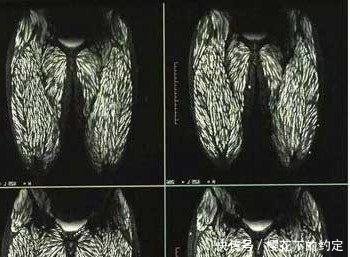

近日,年仅23岁的婷婷(化名),就因生食猪肉出现身体多部位、大面积寄生虫感染。就医医院医生表示,生食肉类极易感染寄生虫,建议市民尽量烹饪加热食用。寄生虫属于蛋白质,一般可通过高温消灭。

通过检查医生发现,婷婷的大脑里也有囊虫钙化现象。“这表示已有囊虫死去,说明囊虫感染的时间已经比较长。而且患者眼球突出,视网膜出血,全身多处感染,还伴有癫痫发作。”省一院神经内科主任医师孟强教授说,这么严重的囊虫感染,他也是第一次遇到。

一部分虫卵在发育成幼虫之后,继而会进入肠壁随后进入血液、淋巴液、肌肉在身体各个部位“安家”就成了“囊虫病”